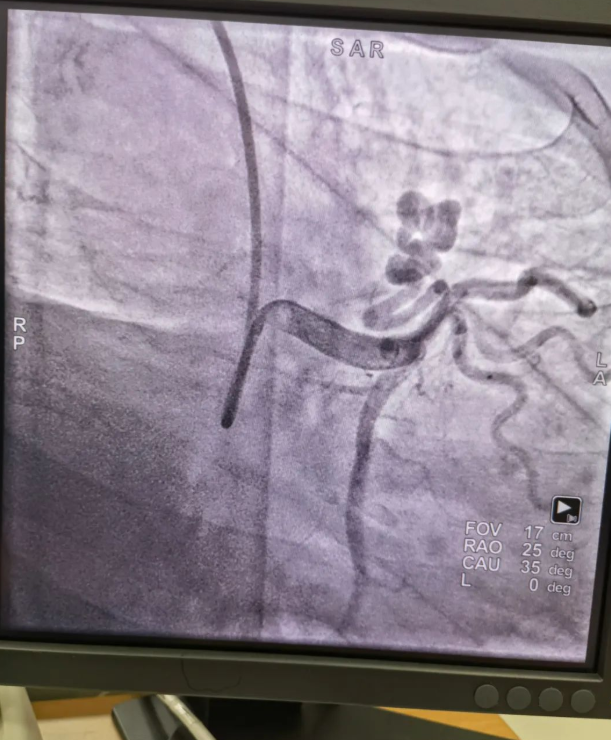

不久前,來自新疆的患者石先生去年至今反復(fù)胸悶、氣短、胸痛,就診于新疆某院,懷疑“冠心病”,住院行冠狀動脈造影術(shù),石先生造影提示“冠狀動脈肺動脈瘺”,而他并非“冠心病”,所以給予的“冠心病”治療,效果不佳。出院后仍反復(fù)出現(xiàn)胸痛、胸悶、氣短等癥狀,經(jīng)親友介紹了解到西安國際醫(yī)學(xué)中心醫(yī)院心臟病醫(yī)院心臟內(nèi)科二病區(qū)曾廣偉主任,多年來潛心研究心臟病介入治療,成功主刀救治了許許多多高危復(fù)雜病例,尤其是在先心病及結(jié)構(gòu)性心臟病封堵,以及冠心病、心律失常射頻消融及起搏治療等方面積累了豐富的診療經(jīng)驗(yàn)。

此病例罕見,在曾廣偉從醫(yī)18年生涯里曾碰到有2個印象深刻的病例,患者分別是53歲和66歲,當(dāng)時建議患者入院進(jìn)行動脈瘺的封堵術(shù),但患者和家屬考慮到這個手術(shù)案例極少,風(fēng)險(xiǎn)也高,均未接受手術(shù)治療建議,只是能采取藥物保守治療,出院后隨訪得知患者癥狀緩解效果不佳,后來在隨訪中也與53歲患者失去了聯(lián)系,而66歲患者因冠狀動脈肺動脈瘺出現(xiàn)反復(fù)心衰,在當(dāng)?shù)蒯t(yī)院藥物治療,短短2年時間,患者因?yàn)閯用}瘺未及時手術(shù)失去了生命。所以此次患者石先生到訪,曾廣偉主任在詳細(xì)掌握病例資料基礎(chǔ)上,果斷建議進(jìn)行動脈瘺的封堵術(shù)治療,為了提高手術(shù)成功率和精準(zhǔn)度,曾廣偉主任搜集相關(guān)診療資料,反復(fù)推演論證,經(jīng)過相當(dāng)充足的準(zhǔn)備工作,于5月18日成功進(jìn)行了封堵手術(shù),完全堵上了瘺口。

患者術(shù)后第2天,已經(jīng)沒有明顯的胸悶、氣短、胸痛等癥狀,目前身體狀態(tài)良好。本次手術(shù)曾廣偉主任及其團(tuán)隊(duì),采取從右手臂一根血管進(jìn)入,并在2小時之內(nèi)完美封堵,創(chuàng)口小,痛苦小。手術(shù)雖然難度大、風(fēng)險(xiǎn)高,相關(guān)案例也少,但是曾廣偉主任主刀即在巔峰,這樣一臺完美的手術(shù)靠的不是運(yùn)氣,是豐富的臨床手術(shù)經(jīng)驗(yàn),扎實(shí)的專業(yè)知識儲備,以及對醫(yī)療事業(yè)的孜孜追求。

冠狀動脈瘺是指冠狀動脈與心腔、冠狀靜脈、肺動脈等的異常連接,是一種少見的先天性心臟病,發(fā)病率為1.3%。而冠狀動脈肺動脈瘺是冠狀動脈與肺動脈之間產(chǎn)生的一種血管性瘺口,導(dǎo)致冠狀動脈里的血液流入肺動脈里,使冠狀動脈里血液流量減少,出現(xiàn)心肌供血不足,冠狀動脈肺動脈瘺會使患者出現(xiàn)胸部疼痛、胸悶、呼吸困難、頭暈、乏力等一系列癥狀,隨著疾病不斷進(jìn)展,可引發(fā)心功能的障礙和心肌缺血,肺動脈會逐漸形成肺動脈高壓,還可能導(dǎo)致動脈瘤的破裂,甚至威脅病人的生命安全,所以早期發(fā)現(xiàn)和治療冠狀動脈肺動脈瘺,對病人的預(yù)后改善具有重要的意義。